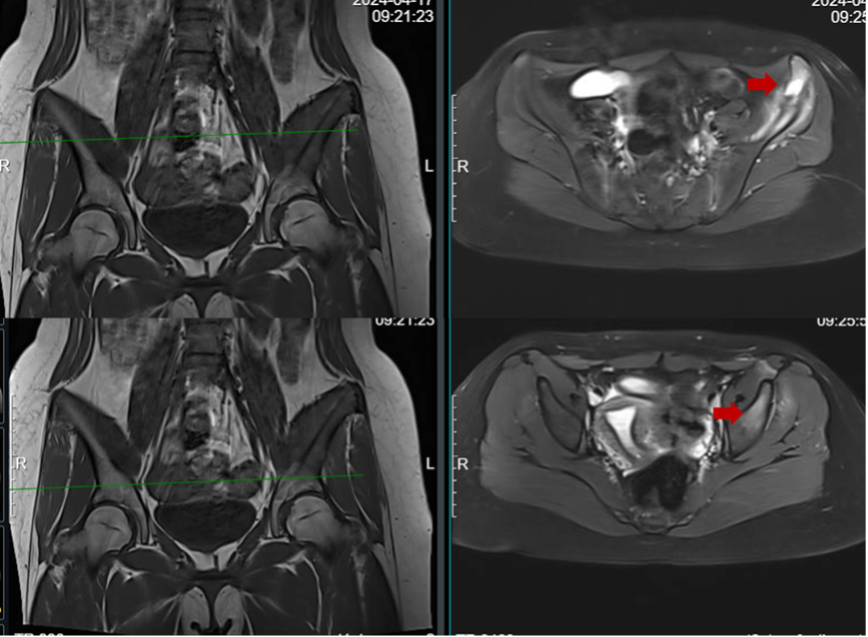

图:骨盆CT提示左侧髂骨翼溶骨性病变伴骨皮质破坏

图:骨盆核磁共振提示左侧髂骨翼病变伴周围软组织水肿